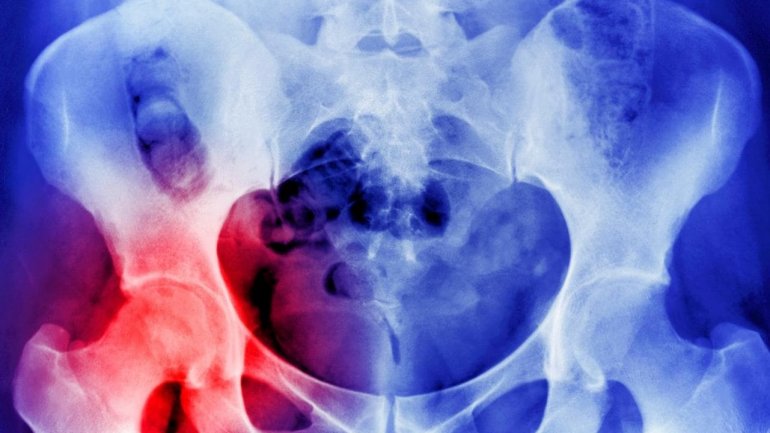

Οι εθελοντές υποβλήθηκαν σε μέτρηση της πυκνότητας των οστών και της οστικής τους αντοχής με τη χρήση μιας νέας, υψηλής ανάλυσης αξονικής τομογραφίας (CT) στον καρπό και στον αστράγαλο, που ονομάζεται XtremeCT και χρησιμοποιείται μόνο για έρευνα.

Το XtremeCT, το οποίο βρίσκεται στο Ινστιτούτο McCaig, είναι το πρώτο του είδους του στον κόσμο και επιτρέπει στους ερευνητές να δουν λεπτομερώς την μικροαρχιτεκτονική των οστών. Εξετάστηκε επίσης η πυκνότητα οστικής απορρόφησης με ακτίνες Χ (DXA). Οι συμμετέχοντες έλαβαν σαρώσεις κατά την έναρξη της μελέτης και στους 6, 12, 24 και 36 μήνες. Για την αξιολόγηση των επιπέδων βιταμίνης D και ασβεστίου, οι ερευνητές συγκέντρωσαν δείγματα αίματος νηστείας στην αρχή της μελέτης και σε 3, 6, 12, 18, 24, 30 και 36 μήνες καθώς και συλλογές ούρων ετησίως.

Οι ενήλικες χάνουν σταδιακά σε οστική πυκνότητα και τα αποτελέσματα της DXA έδειξαν μέτρια μείωση της BMD στη διάρκεια της μελέτης, χωρίς να εντοπίζονται διαφορές μεταξύ των τριών ομάδων. Ωστόσο, η πιο ευαίσθητη μέτρηση της BMD με XtremeCT υψηλής ανάλυσης έδειξε σημαντικές διαφορές στην οστική απώλεια μεταξύ των τριών δοσολογιών.

Η συνολική BMD μειώθηκε κατά την τριετή περίοδο κατά 1,4% στην ομάδα των 400 IU, κατά 2,6% στην ομάδα των 4,000 IU και κατά 3,6% στην ομάδα των 10 000 IU. Το συμπέρασμα ήταν ότι, σε αντίθεση με ό, τι προβλεπόταν, η συμπλήρωση με βιταμίνη D σε δόσεις υψηλότερες από εκείνες που συνιστώνται από κάποιους οργανισμούς δεν σχετίστηκε με αύξηση της οστικής πυκνότητας ή της αντοχής των οστών αλλά το αντίθετο. Το XtremeCT ανίχνευσε μια σχετιζόμενη με τη δόση μείωση της οστικής πυκνότητας και η μεγαλύτερη μείωση που παρατηρήθηκε ήταν στην ομάδα των 10.000 IU ημερησίως.